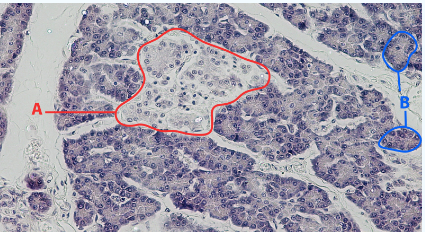

A

Islet

B

Acinar cells

Area

Pancreas